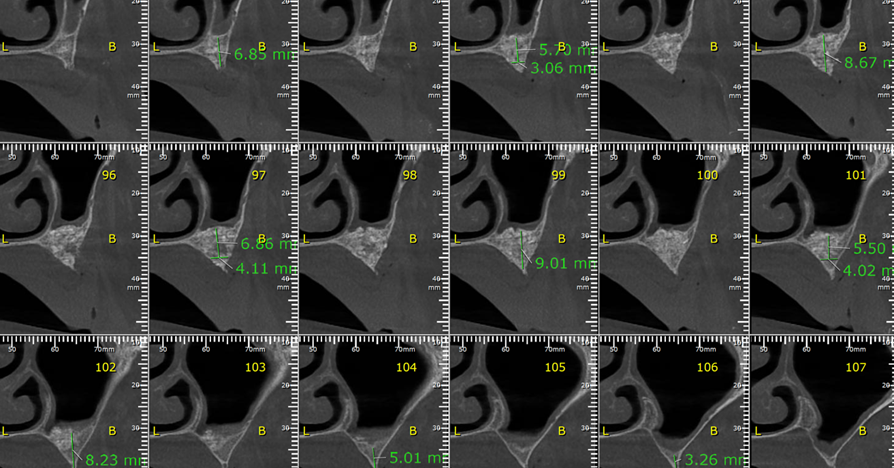

Aguardado o tempo de Osseointegração do enxerto (em torno de oito meses), solicitamos uma nova tomografia, onde foi observado ganho ósseo suficiente para a instalação de implantes, apesar de ainda ser uma condição limítrofe (Fotos 2, 3 e 4). O planejamento cirúrgico foi de instalar cinco implantes, sendo dois no lado direito e três no lado esquerdo, onde a extensão de ganho ósseo foi maior e possibilitava distribuir melhor os implantes.